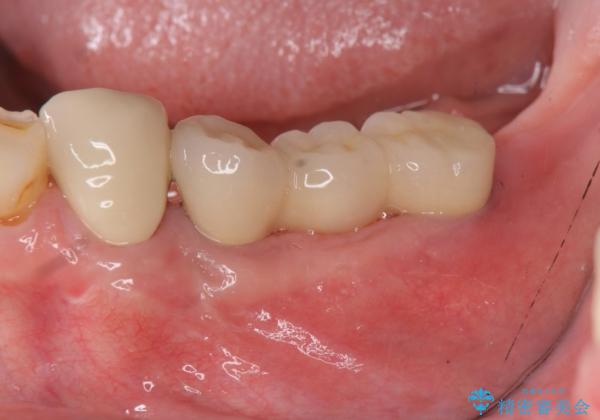

咬合機能を回復し、満足して食事を行えるようインプラント治療を計画します。

- 80万円(インプラント×2・アバットメント×2・ジルコニアクラウン×3)費用は治療当時の料金となります

そのような場合、歯牙欠損状態の放置もしくはインプラント治療の選択になりますが残っている歯への負担も大きいためインプラント治療による咬合機能回復を推奨しております。